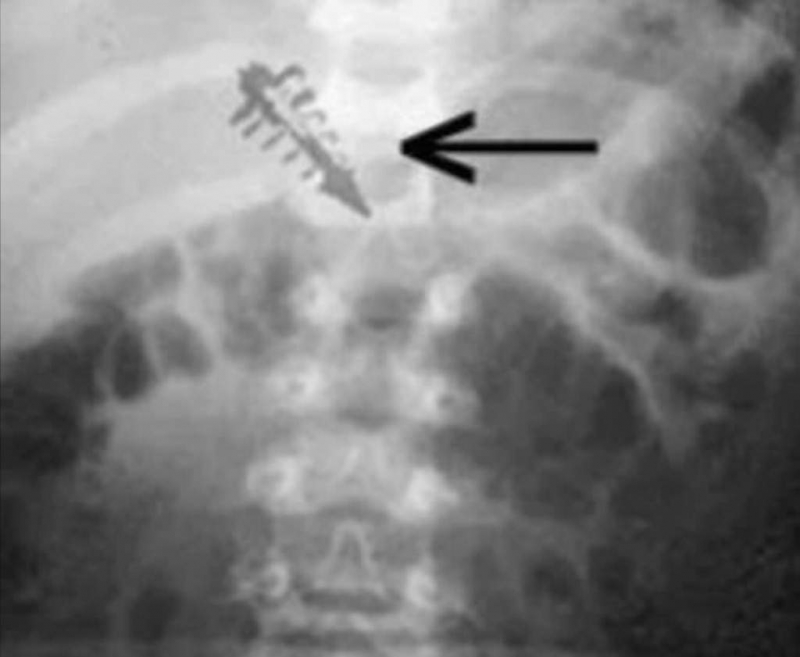

Ảnh chụp X-quang cho thấy vật thể lạ được cấy vào thân thể nạn nhân nói rằng họ bị người ngoài hành tinh bắt cóc. (Ảnh: mufon.com)

TS. Leir cho biết ông không hề nhìn thấy bất kỳ vết sẹo hoặc bất kỳ sự gián đoạn nào tại vùng da mà thiết bị được cấy ghép. Không có dấu hiệu viêm nhiễm, nhưng trên phim X-quang, thiết bị kỳ lạ này lại được nhìn thấy rõ.